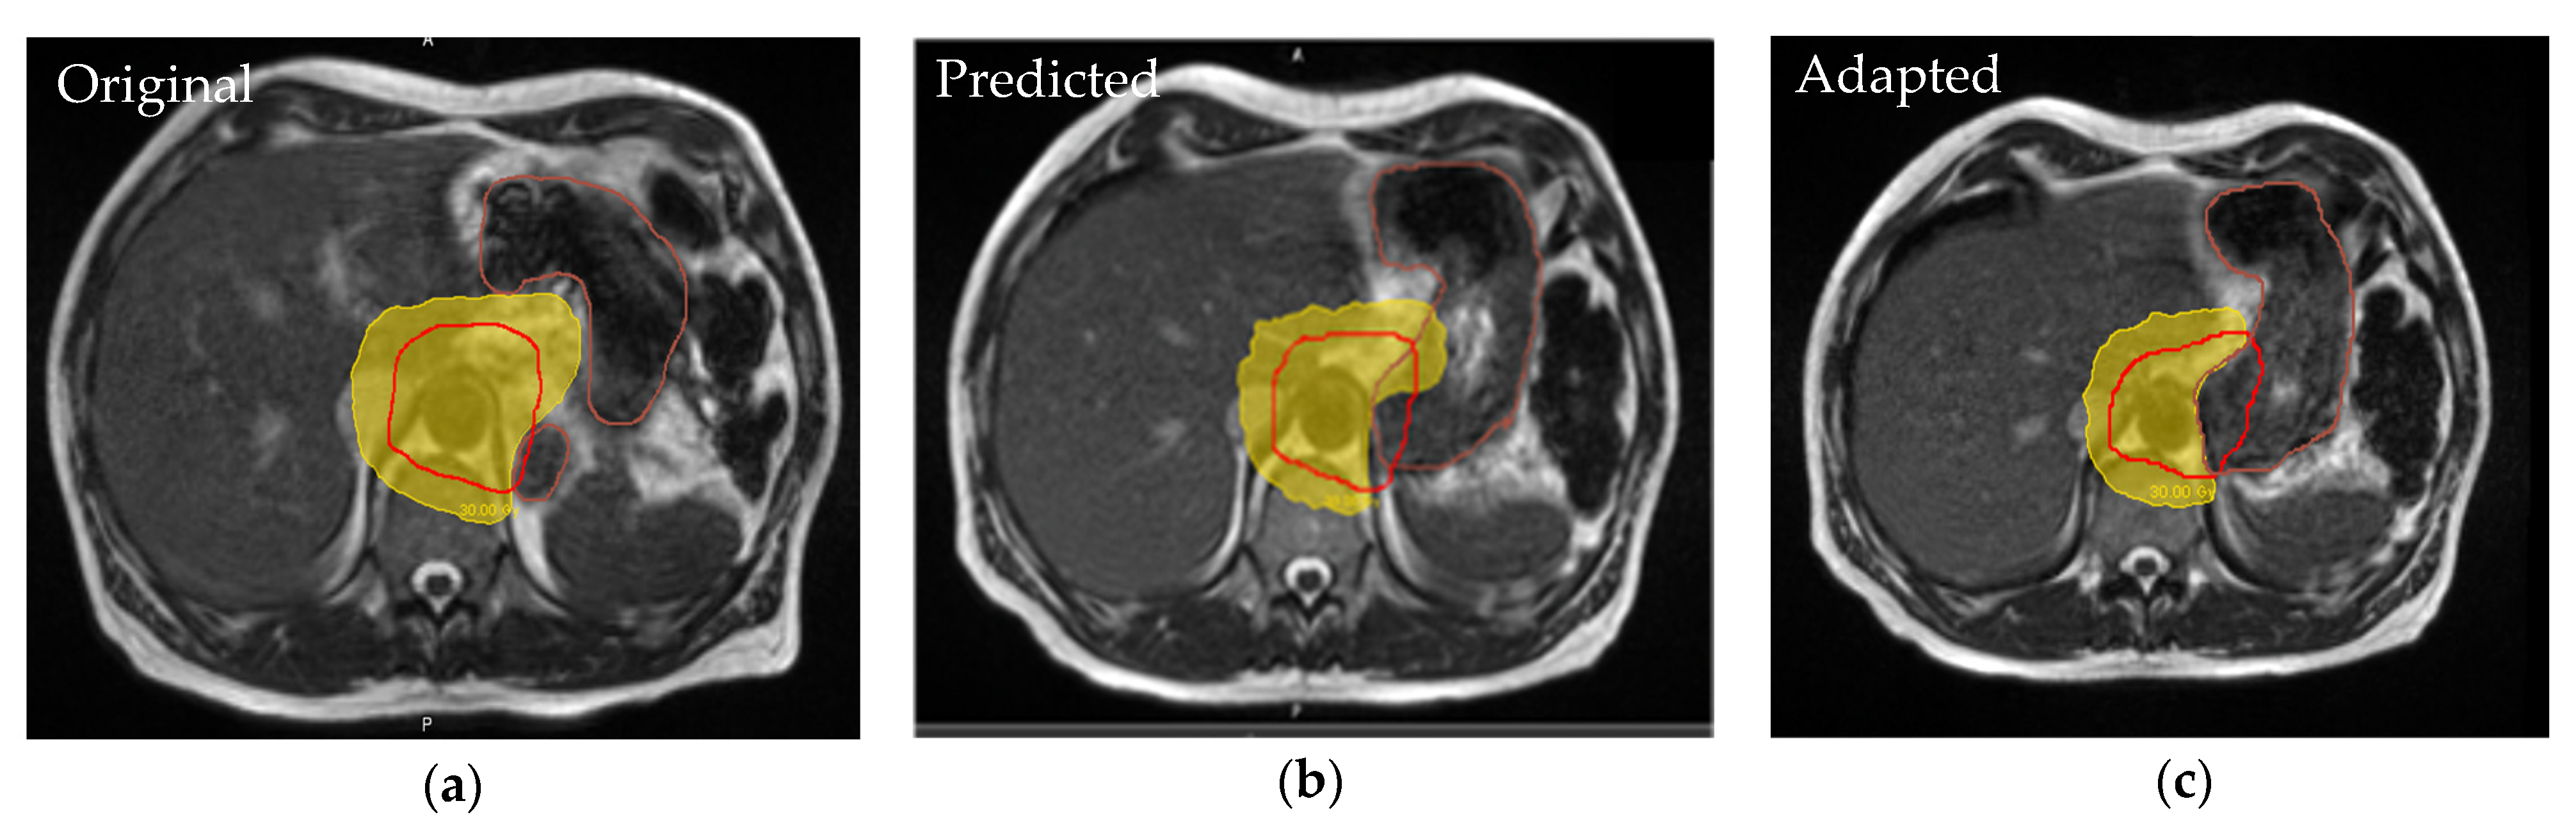

- Placidi, L.; Romano, A.; Chiloiro, G.; Cusumano, D.; Boldrini, L.; Cellini, F.; Mattiucci, G.C.; Valentini, V. On-line adaptive MR guided radiotherapy for locally advanced pancreatic cancer: Clinical and dosimetric considerations. Tech. Innov. Patient Support. Radiat. Oncol. 2020, 15, 15–21. [Google Scholar] [CrossRef] [PubMed]

- Rudra, S.; Jiang, N.; Rosenberg, S.A.; Olsen, J.R.; Roach, M.C.; Wan, L.; Portelance, L.; Mellon, E.A.; Bruynzeel, A.; Lagerwaard, F.; et al. Using adaptive magnetic resonance image-guided radiation therapy for treatment of inoperable pancreatic cancer. Cancer Med. 2019, 8, 2123–2132. [Google Scholar] [CrossRef]

- Chuong, M.D.; Bryant, J.; Mittauer, K.E.; Hall, M.; Kotecha, R.; Alvarez, D.; Romaguera, T.; Rubens, M.; Adamson, S.; Godley, A.; et al. Ablative 5-Fraction Stereotactic Magnetic Resonance-Guided Radiation Therapy With On-Table Adaptive Replanning and Elective Nodal Irradiation for Inoperable Pancreas Cancer. Pract Radiat. Oncol. 2021, 11, 134–147. [Google Scholar] [CrossRef]

- Hassanzadeh, C.; Rudra, S.; Bommireddy, A.; Hawkins, W.G.; Wang-Gillam, A.; Fields, R.C.; Cai, B.; Park, J.; Green, O.; Roach, M.; et al. Ablative Five-Fraction Stereotactic Body Radiation Therapy for Inoperable Pancreatic Cancer Using Online MR-Guided Adaptation. Adv. Radiat. Oncol. 2021, 6, 100506. [Google Scholar] [CrossRef]